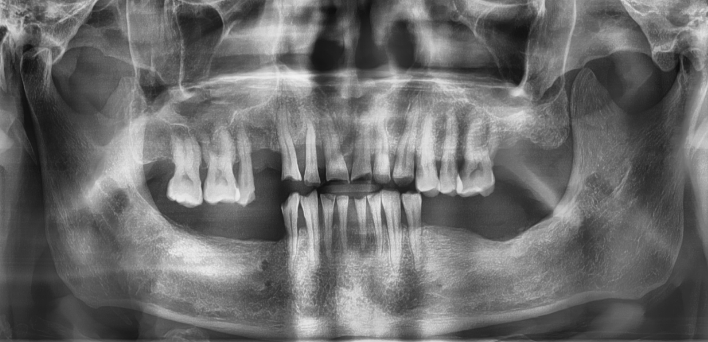

임플란트 : 손 ** 님 (50대)

Before Before

2020.02.30

After After

※ 더서울치과의원은 의료법을 준수하며 위 케이스는 실제 환자의 동의를 얻은 사례로 치료 전, 후가 동일한 환경에서 촬영되었습니다.

환자 케이스에 따라 부작용이 발생할 수 있습니다. 이 부분은 의료진의 충분한 상담과 체크를 통해 예방하고 줄일 수 있습니다.

[임플란트 부작용] 수술 후 관리가 소홀할 경우 출혈, 주위염 등의 부작용이 발생할 수 있어 구강 위생을 철저히 유지하고, 정기적인 검진을 통해 상태를 점검하는 것이 중요합니다.

환자 특징

환자 특징01무치악 상태

환자 특징02수년간 무치악으로 지내심

임플란트가 불가능할것이라

생각하고 내원

위, 아래 6개씩 식립

디지털 풀아치 임플란트